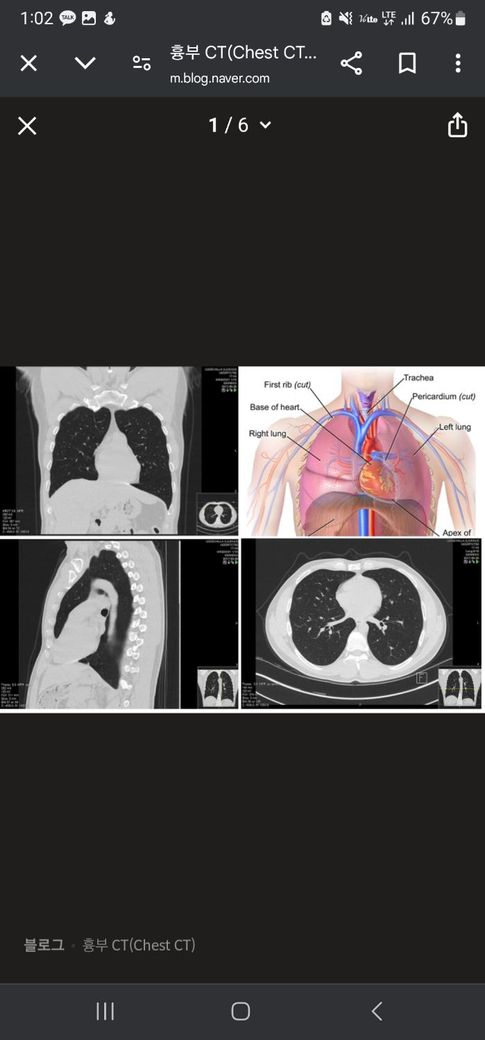

ct 촬영은 사진 속 4번째에 해당하는 axial 사진이 기본적인 촬영 방법입니다.

이 영상을 토대로 1번, 3번 사진을 재구성하여 볼 수 있게 합니다.

CT 판독은 원래 axial plane 으로 합니다. 이게 자세하게 관찰하는 plane입니다 (4번사진)

그리고 편의성을 위해서 coronal plane을 봅니다 (1번 사진) 아무래도 직관적이니까요

sagittal plane의 경우 (3번 사진) 찍을 수야 있겠지만 저는 본적이 없는 것 같습니다.

• 일반적으로 흉부 CT 검사를 시행할 경우 사진으로 올리신 것처럼 아래쪽에서 본 모습, 앞에서본 모습, 옆에서 모습 세 가지가 확인이 가능합니다. 다만 촬영 중 세팅을 어떻게 하였는지에 따라서 측면부는 안 나오는 것도 그럴 수 있긴 하겠습니다. 보통은 측면부까지 나오도록 하는 것이 일반적인데, 촬영한 병원측에 한 번 문의해보시는 것이 좋겠습니다.